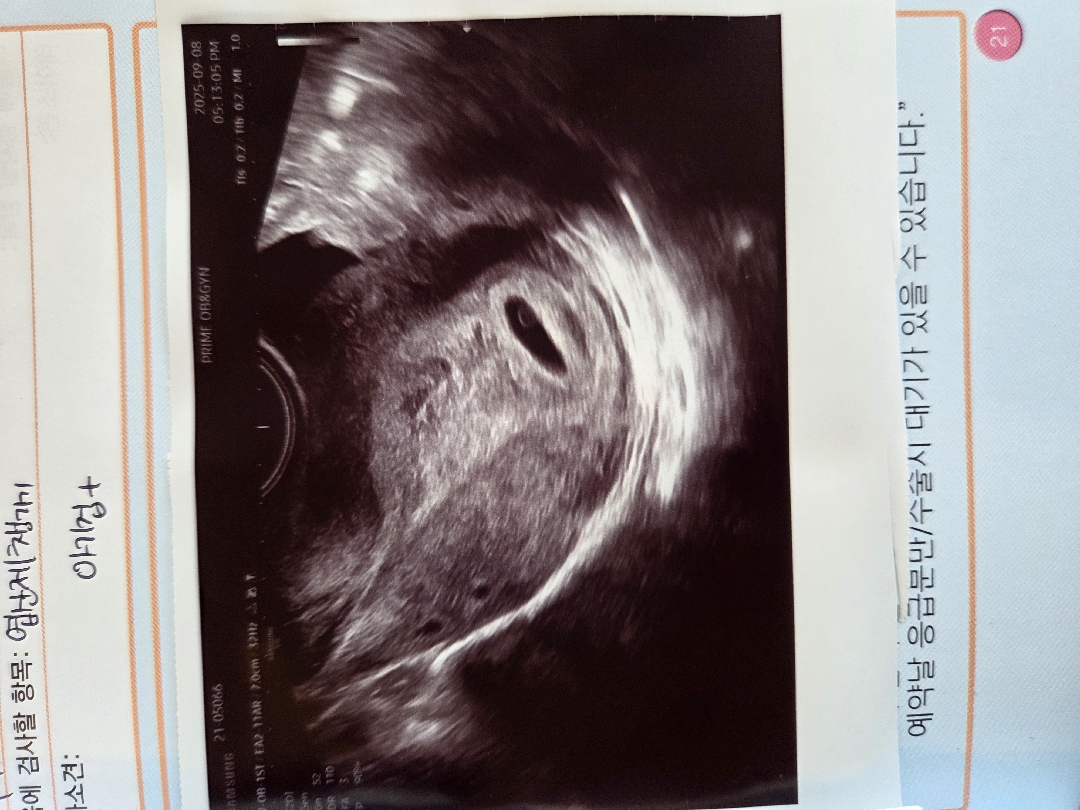

어제 5주0일차 아기집+난황봤어요

4주2일에 아기집 보고난후 갈색혈+ 어젠 선홍색혈 나오길래 병원갔는데 너무 예쁘게 집 잘 지어났네용 행복합니당😍 다들 행복하세용❣️